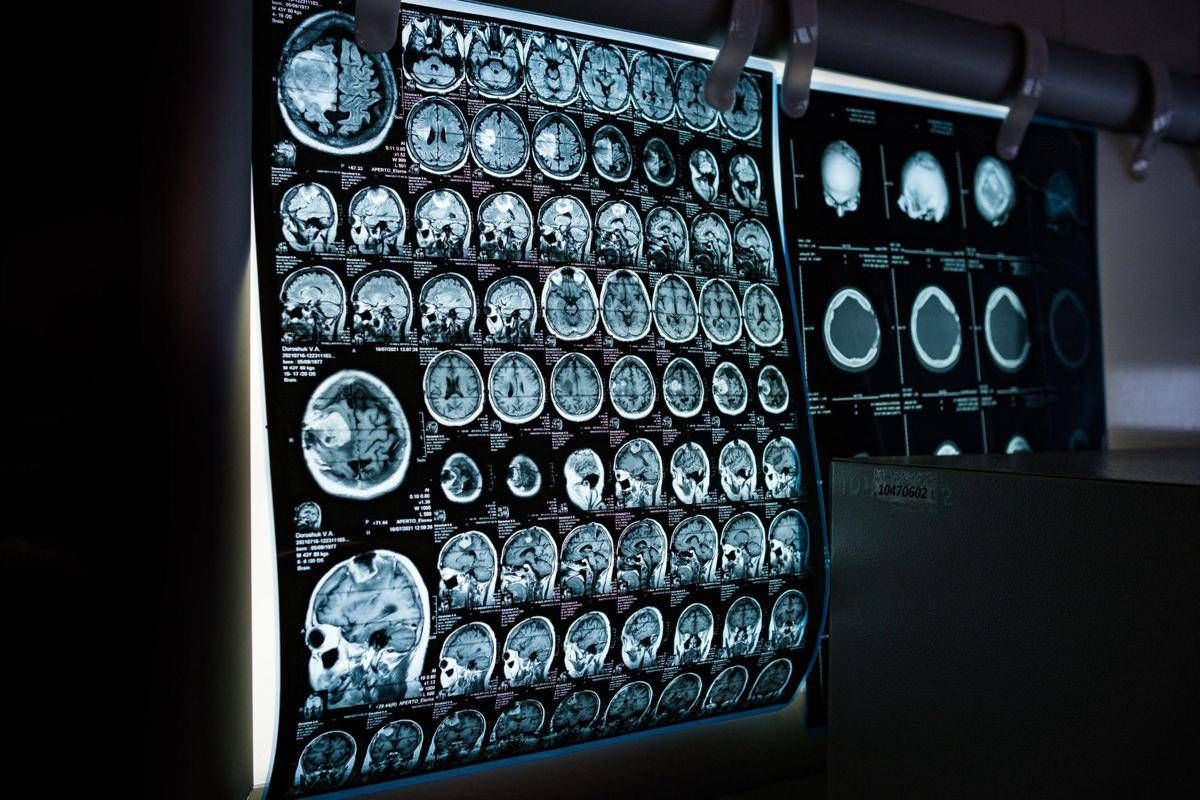

Uno spray nasale testato sui modelli animali potrebbe invertire l’invecchiamento del cervello con sole 2 dosi, riducendo drasticamente l’infiammazione cerebrale, ripristinando le centrali energetiche cellulari del cervello e migliorando così significativamente la memoria. Un processo di ringiovanimento che agirebbe nel giro di poche settimane per durare mesi.

E’ il risultato dello studio condotto dai ricercatori della Texas A&M University (Naresh K. Vashisht College of Medicine) negli Stati Uniti. Lo spray contiene minuscole particelle biologiche note come vescicole extracellulari (Ev), che agiscono come veicoli di consegna con a bordo un potente carico genetico, i microRna. Le sostanze aggirano lo scudo protettivo del cervello e viaggiano direttamente nel tessuto cerebrale, dove vengono assorbite. Arrivati a destinazione nelle cellule immunitarie residenti nel cervello, i microRna ‘spengono’ i sistemi noti per essere responsabili dell’infiammazione cronica nel cervello che invecchia.

Per spiegare il senso di questo processo, gli scienziati invitano a immaginare il cervello come un motore ad alte prestazioni: nel corso dei decenni questo motore non solo si usura, ma inizia anche a surriscaldarsi. Piccoli ‘focolai’ di infiammazione covano nelle profondità del centro della memoria, creando una persistente nebbia mentale (brain fog) che rende più difficile pensare, formare nuovi ricordi o persino adattarsi a nuovi ambienti, aumentando al contempo il rischio di disturbi come il morbo di Alzheimer. Questo processo a lenta combustione viene chiamato neuroinfiammazione. E per decenni si è pensato che fosse il prezzo inevitabile dell’invecchiamento. Ma il nuovo studio, pubblicato sul ‘Journal of Extracellular Vesicles’, suggerisce che l’ondata infiammatoria potrebbe essere reversibile.

Il team guidato da Ashok Shetty, distinguished professor dell’ateneo e associate director dell’Istituto di medicina rigenerativa, insieme ai ricercatori senior Madhu Leelavathi Narayana e Maheedhar Kodali, ha sviluppato lo spray nasale e ha verificato che a livello cellulare il trattamento ha ricaricato i mitocondri neuronali, ovvero le centrali energetiche che si trovano all’interno delle cellule cerebrali. La terapia ha dissipato la nebbia mentale e ha anche migliorato fisicamente la capacità del cervello di elaborare e immagazzinare informazioni.

“Stiamo ridando vitalità ai neuroni riducendo lo stress ossidativo e riattivando i mitocondri del cervello”, evidenzia Narayana. Nei modelli trattati, i test comportamentali hanno confermato i risultati biologici, mostrando notevoli miglioramenti non solo nel riconoscimento di oggetti familiari, ma anche nell’individuazione di nuovi oggetti e di cambiamenti nell’ambiente circostante, in netto contrasto con il gruppo di controllo.

“Le malattie legate all’invecchiamento cerebrale, come la demenza, rappresentano un grave problema di salute a livello mondiale – sottolinea Shetty – Quello che stiamo dimostrando è che l’invecchiamento cerebrale può essere invertito, aiutando le persone a mantenere la mente lucida, a rimanere socialmente attive e a non subire il declino cognitivo legato all’età”. Lo studio suggerisce un’ampia applicabilità dello spray. I risultati del trattamento, illustra Shetty, “sono stati coerenti e simili in entrambi i sessi”. La modalità di somministrazione “è uno degli aspetti più interessanti del nostro approccio”, commenta Kodali. “La somministrazione intranasale ci permette di raggiungere e trattare il cervello direttamente, senza ricorrere a procedure invasive”.

Quanto agli effetti, quella che si osserva è “l’attivazione dei sistemi di riparazione del cervello, che guariscono l’infiammazione e si rigenerano”, suggerisce Shetty. Sono ovviamente necessarie ulteriori ricerche per confermare questi risultati, ma Shetty e il suo team hanno già depositato un brevetto negli Stati Uniti per la terapia. Il lavoro è stato portato avanti con il sostegno del National Institute on Aging (Nia).